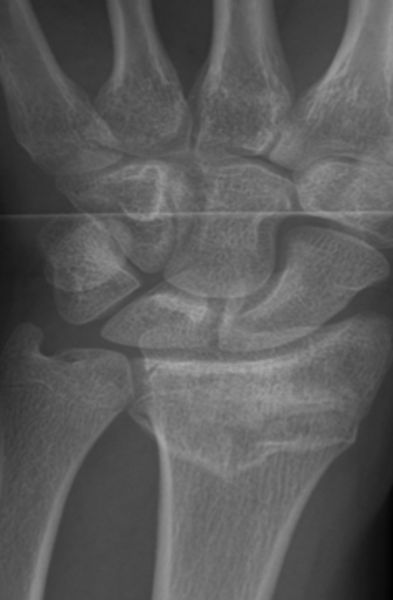

Besteht der klinische Verdacht auf eine distale Radiusfraktur wird zunächst ein Röntgenbild des Handgelenks in 2 Ebenen angefertigt. Bei schwereren Bruchformen sollte eine Computertomographie (CT) erfolgen um die weitere Therapie optimal planen zu können. In einigen Fällen, insbesondere bei Verdacht auf ligamentäre Begleitverletzungen (Verletzungen von Bandstrukturen im Handgelenks- und Handwurzelbereich), sollte eine Magnetresonanztomographie (MRT oder auch Kernspin genannt) durchgeführt werden.

Unterteilen lässt sich der Bruch nach dem Unfallhergang, nämlich ob der Bruch auf die ausgestreckte Hand (Extensionsfraktur oder auch Colles Fraktur) oder auf die gebeugte Hand (Flexionsfraktur oder auch Smith Fraktur) erfolgt ist. Daneben werden noch weitere Einteilungen vorgenommen, beurteilt wird hier, ob der Bruch ohne Gelenkbeteiligung, mit teilweise Beteiligung des Handgelenks  oder einer Trümmerfraktur des Handgelenks einhergeht.